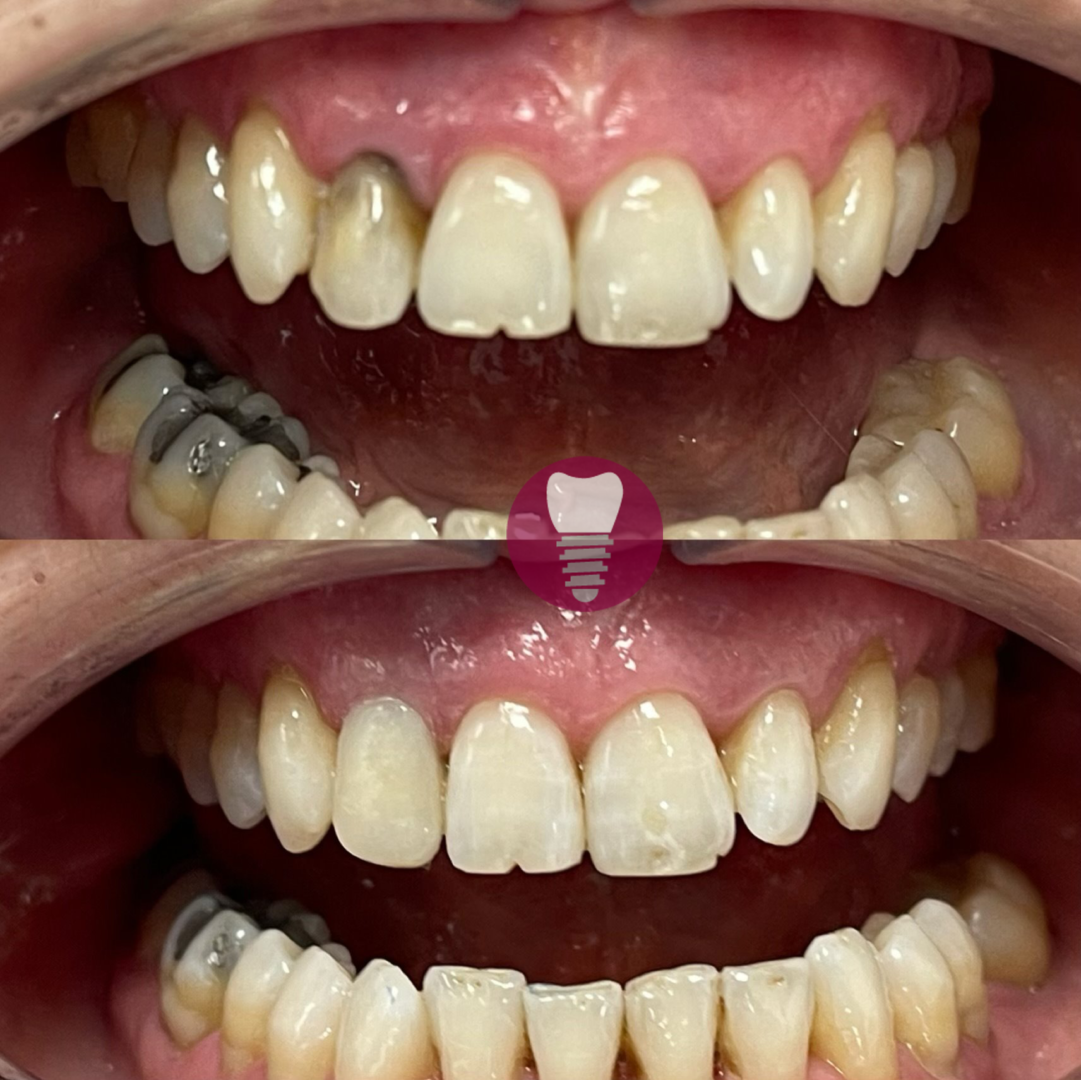

4.1 – Implante dental de incisivo superior

Los implantes dentales son una solución avanzada para la pérdida de piezas dentales. Este procedimiento consiste en la colocación de una raíz artificial de titanio en el hueso maxilar, sobre la cual se instala una corona dental personalizada que imita a la perfección la forma y color del diente original. Este tratamiento es ideal para restaurar incisivos superiores, devolviendo la funcionalidad y estética de la sonrisa de manera natural y duradera.